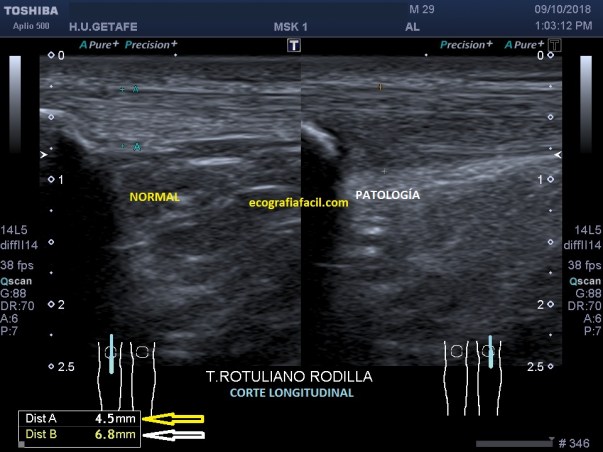

Torsión testicular: Se produce cuando los testículos y el cordón espermático giran una o más veces, obstruyendo el flujo sanguíneo. El diagnóstico depende de la capacidad de confirmar la ausencia de flujo sanguíneo en el testículo doloroso. El testículo está aumentado de tamaño e hipoecogénico, con una imagen de relativa heteoecogenicidad, por el edema y presenta una orientación anormal dentro del escroto. Puede verse afectado todo e teste o una porción, imagen 13 y 14 respectivamente.